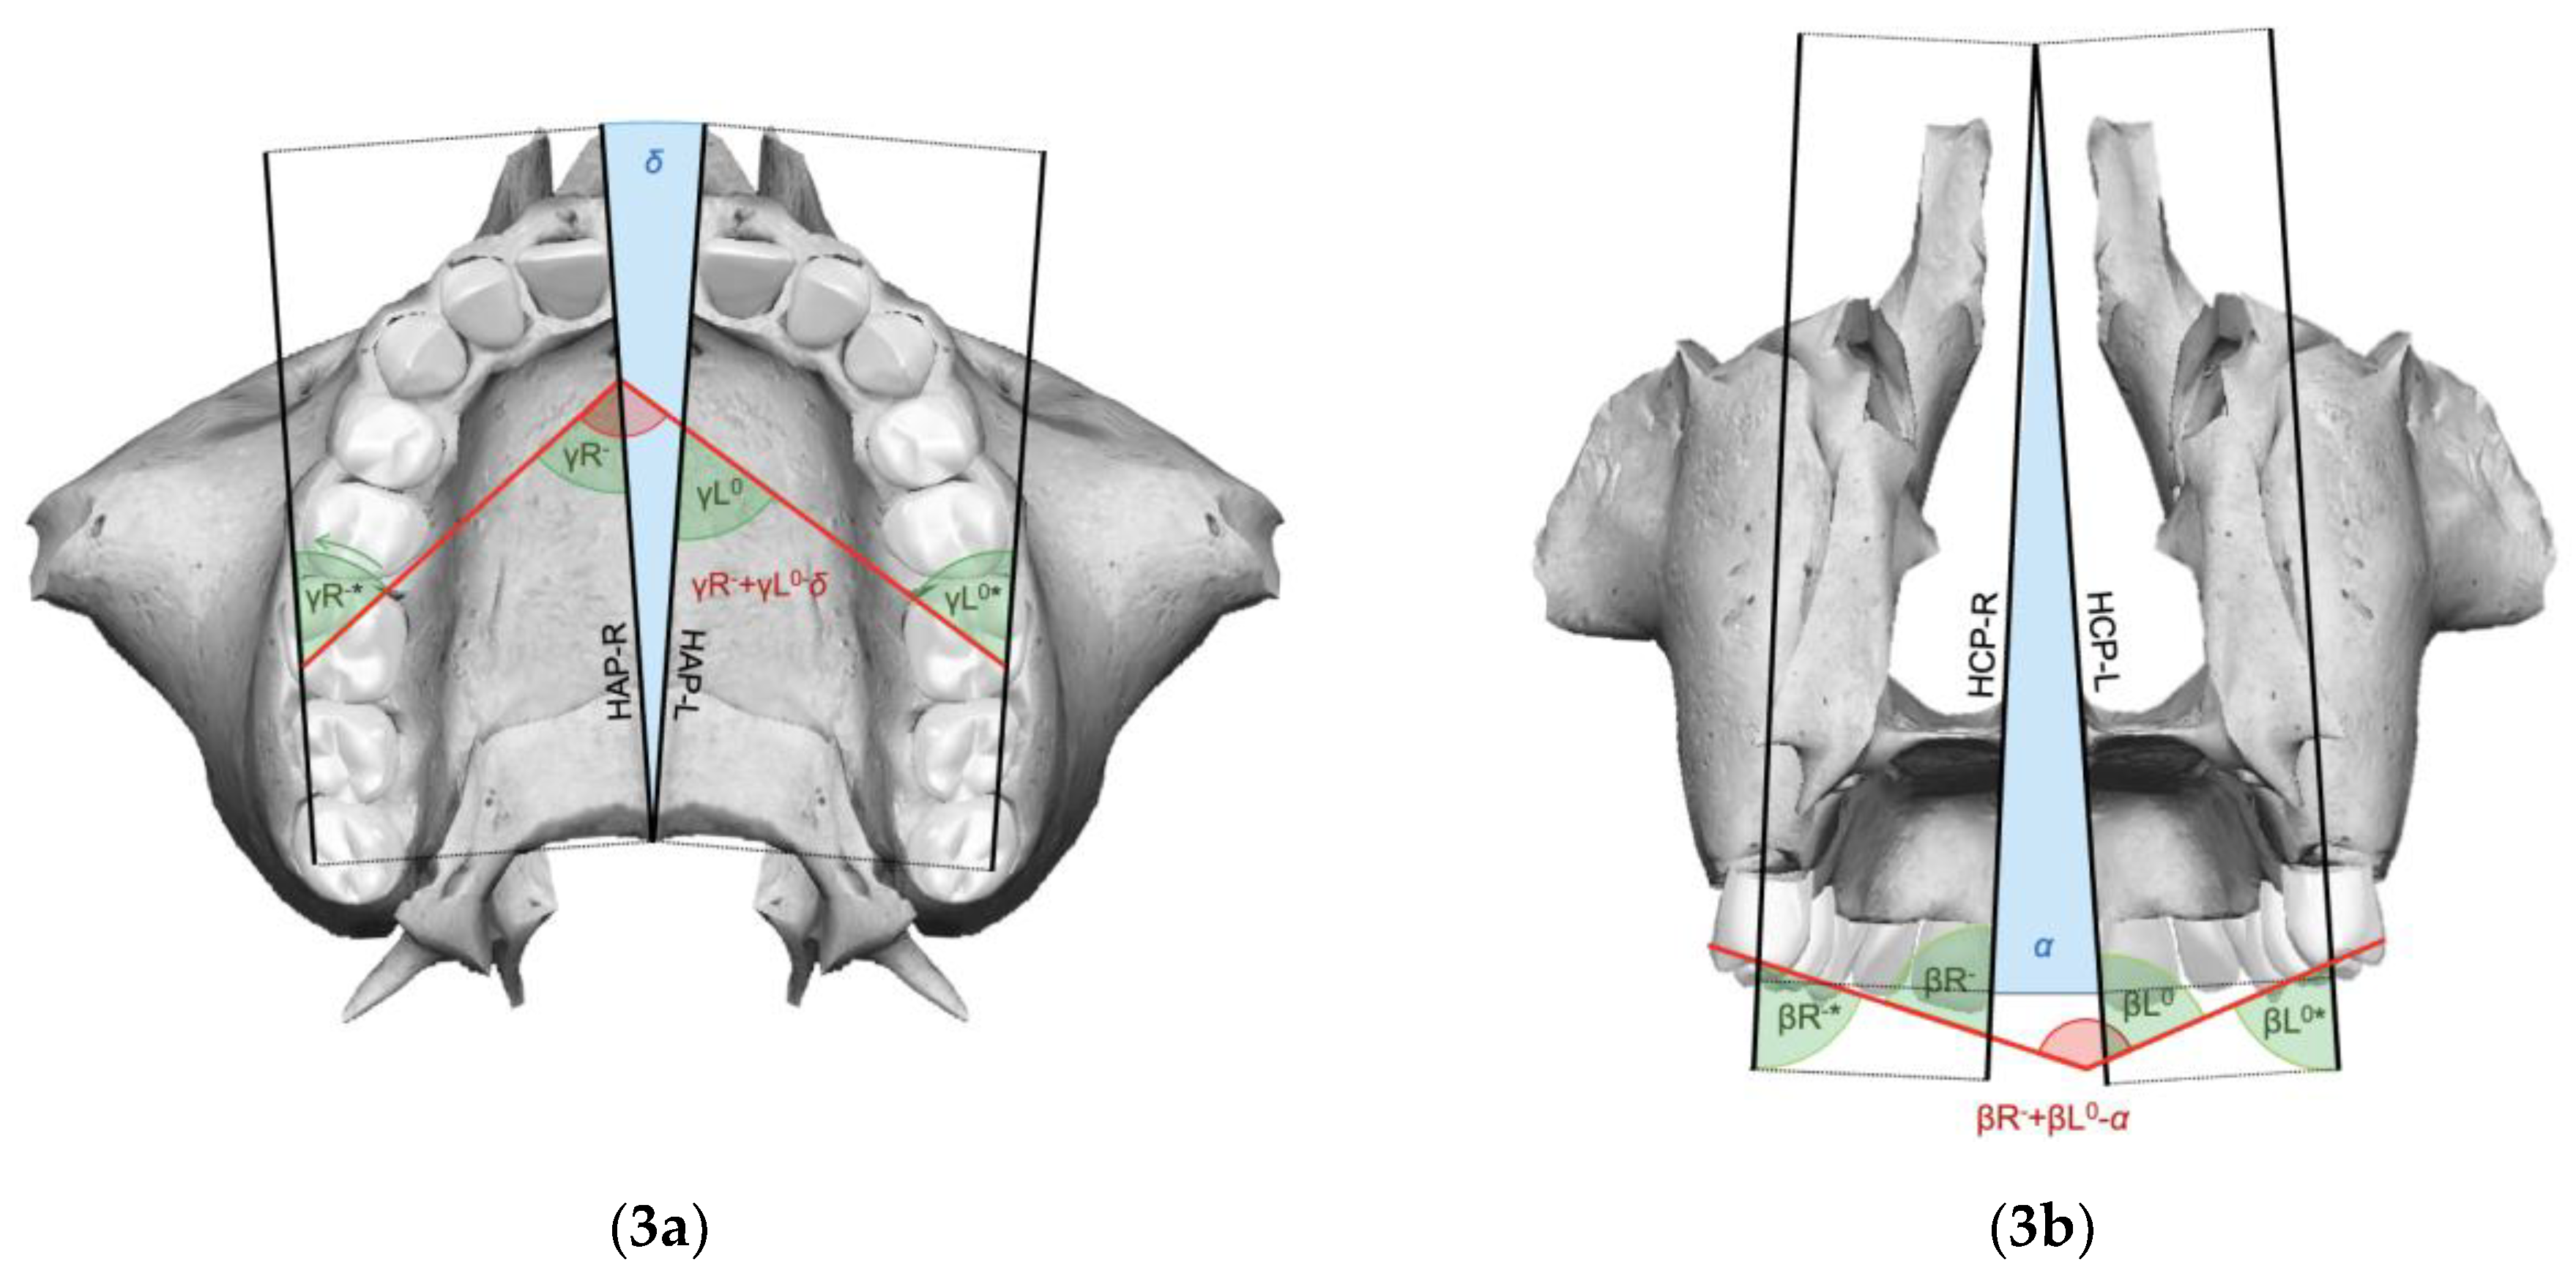

- For clinical improvements to be achieved in the expansion phase, it is necessary that the molar rotation angle (γ) and the intermolar angle (β) at the end of expansion are less than the difference between the respective pre-treatment angle and the orthopedic expansion angle.

- It is possible to calculate expansion angles (α and δ) by a reliable and reproducible method, respecting radiation protection principles, without requiring post-expansion CBCT scans, with the following formulas:

| Orthopedic expansion angle on frontal view (α) | Angle corresponding to the pyramid-like splaying pattern of the post-expansion maxillary components, projected on the frontal view |

| Orthopedic expansion angle on axial view (δ) | Angle corresponding to the pyramid-like splaying pattern of the post-expansion maxillary components, projected on the axial view |

| Molar angle of rotation (γ) | Angle formed by the intersection of the lines passing over the tips of the MPC and the DBC of the right and left maxillary upper first molars |

| Right molar angle of rotation (γR) | Angle formed by the intersection of the line passing over the MPC and the DBC tips of the right maxillary upper first molar and the Ans-Pns segment |

| Left molar angle of rotation (γL) | Angle formed by the intersection of the line passing over the MPC and the DBC tips of the left maxillary upper first molar and the Ans-Pns segment |